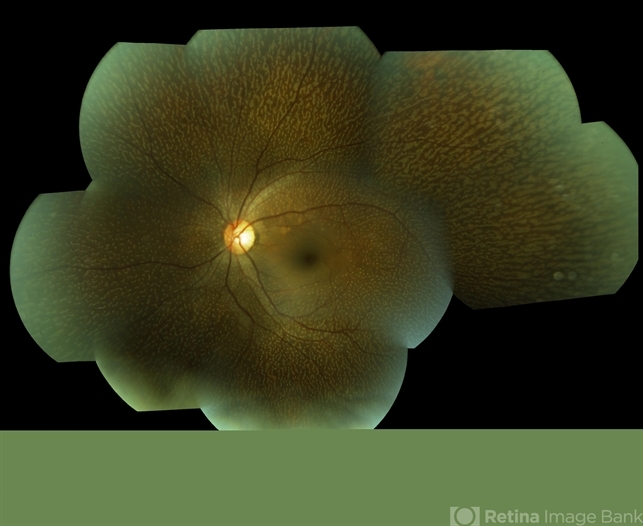

- Fundus Albipunctatus

- Fundus albipunctatus.